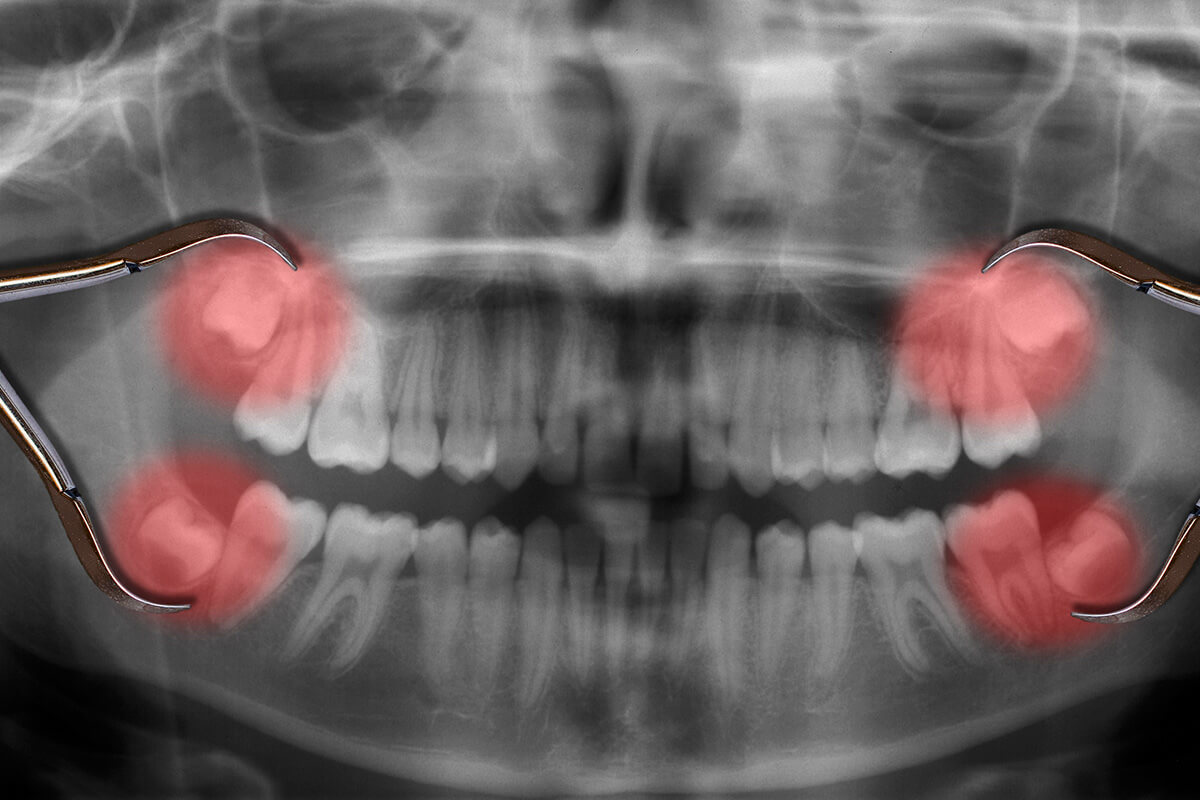

Wisdom Teeth Extractions

Removal of impacted or problematic wisdom teeth to prevent pain and infection.

✔ Treat impacted wisdom teeth before complications arise